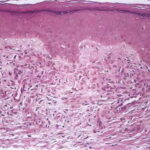

The variable epidermis may be hyperkeratotic with focal parakeratosis, acanthotic to atrophic, and with focal spongiosis. There is proliferation of small blood vessels in the papillary dermis, forming lobular aggregates {glomeruloid proliferation}. The proliferation may be florid, mimicking Kaposi’s sarcoma {acroangiodermatitis} . There is a superficial perivascular lymphocytic infiltrate that surrounds thickened capillaries and venules. The reticular dermis is often fibrotic. Extravasated erythrocytes and hemosiderin are usually present superficially, but they may be identified about the deep vascular plexus as well. Fibrin thrombi may be observed in the small vessels, likely reflecting flow disruption and anoxia. They do not indicate a concurrent coagulopathy. Endothelial necrosis and neutrophils may be present as well, reflecting similar changes, and do not indicate a leukocytoclastic vasculitis